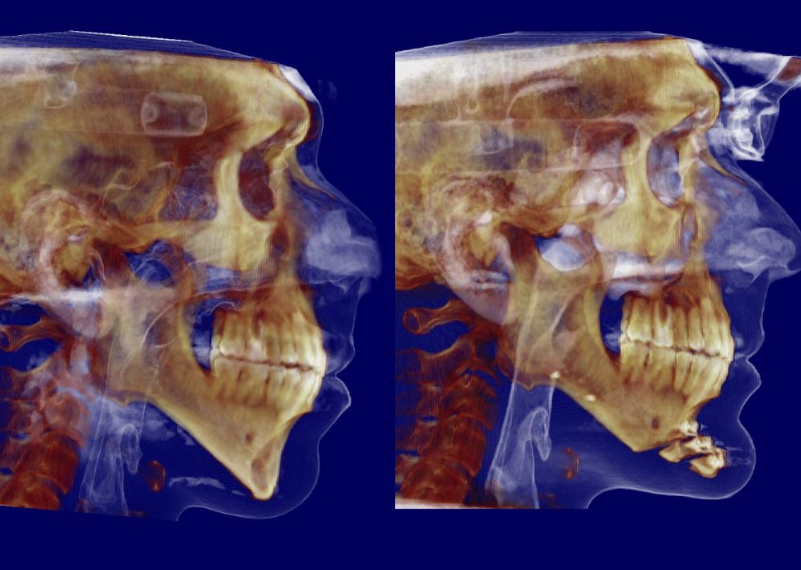

Lets be clear this is not hate, but doing bonegraft helps with not creating step offs and filling in gaps of leforts and bsso obv. Most of the time the gaps will be filled nonetheless to some degree but bone grafts is more of a guarntee. Also alfaro has many patients i have been in contact with where the bone didnt get healed fully because of huge movements and no bonegrafting and only anterior plates, ram does kinda the same except he dont do the same big movements.

And its more important if you do big bsso cuts, genios or maybe the most important one for big downgrafts of the maxilla.

Also some people might say that bonegraft dont show in ct/cbct, it def does

look in the pic below for example at the cuts shown with red circle:

Also some people might say that bonegraft dont show in ct/cbct, it def does

look in the pic below for example at the cuts shown with red circle: